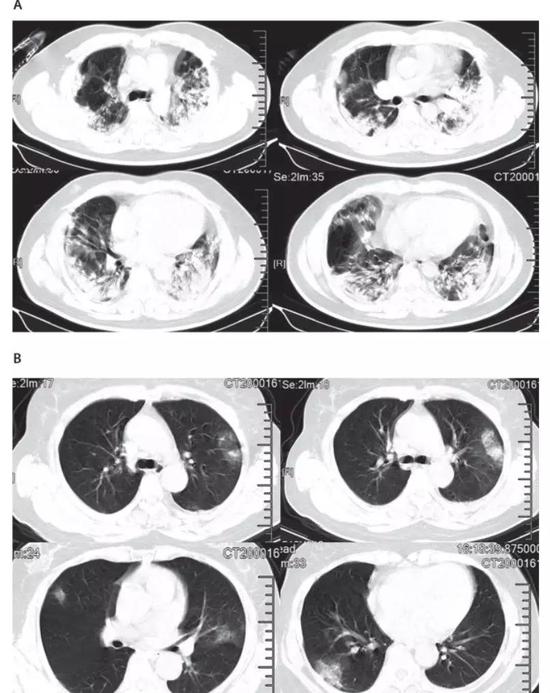

肺部CT异常是本次新型冠状病毒肺炎最典型的影像学表现。在41例患者中,有40例出现双侧肺叶受累,重症患者肺部CT的典型表现为双侧多小叶和亚段实质性病变,轻症患者的代表性CT表现为双侧节段性毛玻璃样变。

A为ICU患者,B为非ICU患者/图源《柳叶刀》